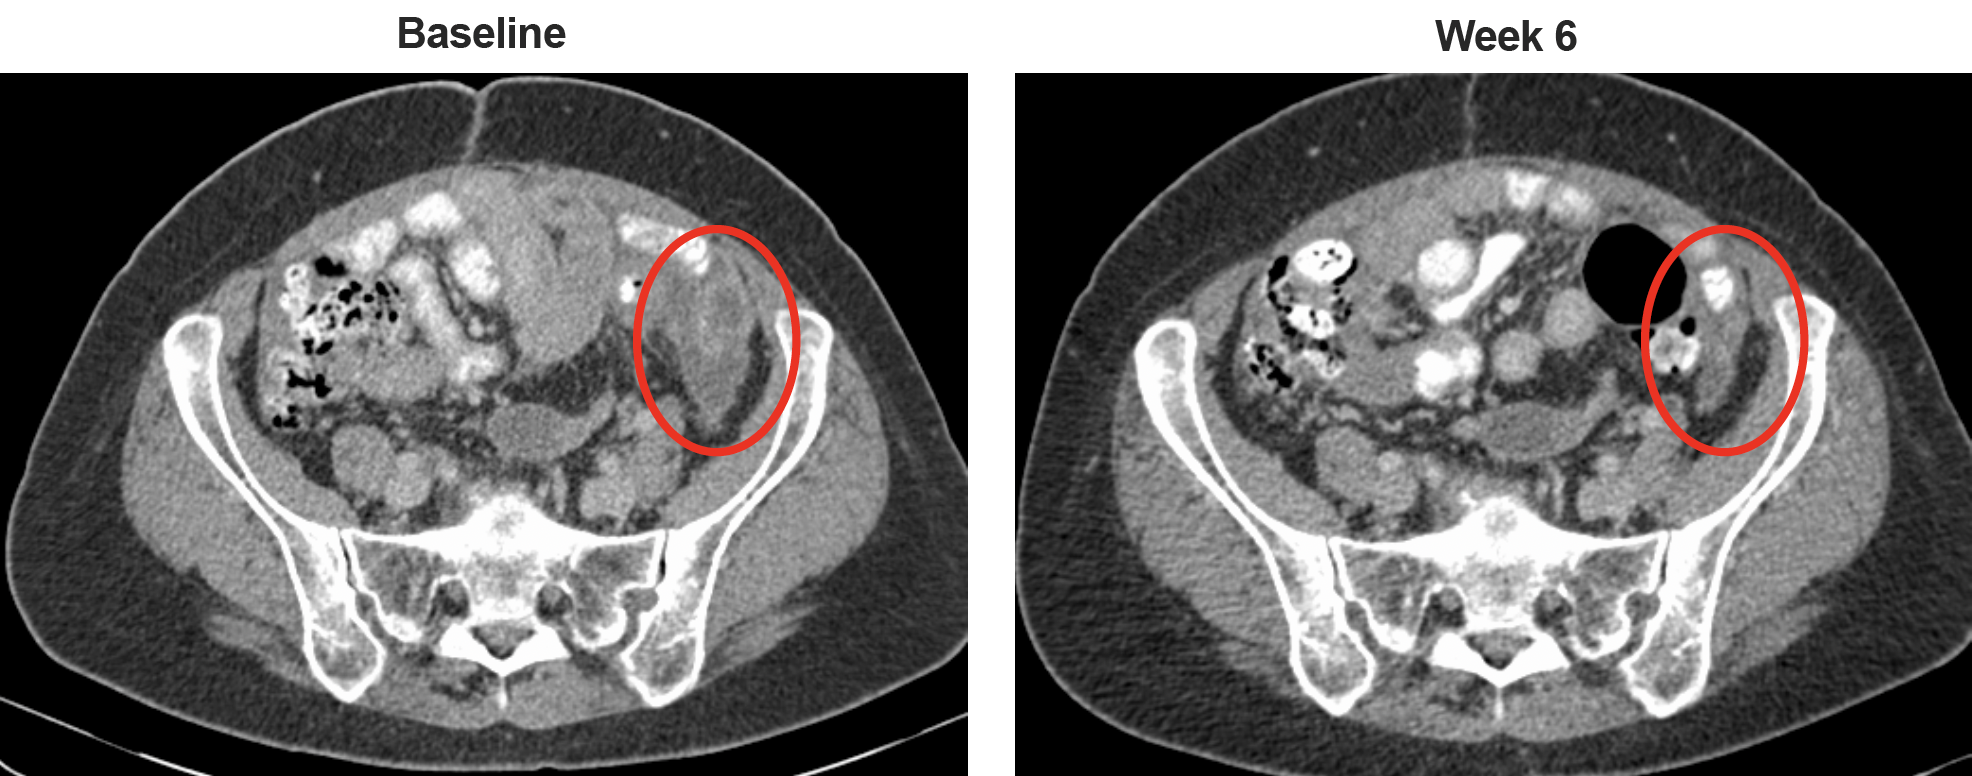

The starting flat dose was very low (70μg), based on the low endogenous levels of circulating IgE and on its very high affinity for Fce receptors. Dose was safely escalated to 12mg. Urticaria was the commonest toxicity, and this was transient and well tolerated. The overall safety profile was tolerable and maximum tolerated dose was not reached, with evidence of anti-tumour activity observed in a patient with ovarian cancer.

Figure 3. Anti-tumour activity of MOv18 IgE. CT images for a patient with ovarian cancer at baseline and week 6 of treatment showing reduction of a peritoneal tumour deposit.